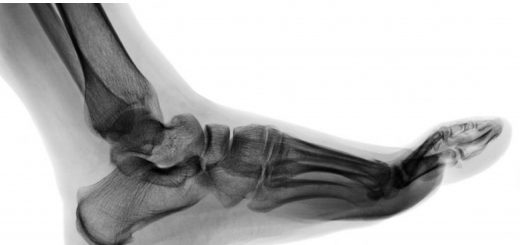

Questa curvatura mantiene le ultime tre falangi (prossimali, intermedie e distali) del piede, cioè le nostre dita, in particolare l’alluce, costantemente in posizione dorsiflessa (cioè flessa verso il dorso del piede, la parte superiore).

Come mai? Perchè questa inclinazione facilita la capacità di rullata in appoggio, sia durante la camminata sia, ancor più, in corsa.

Questa mossa astuta, in realtà, indica una sfiducia “antica” e specifica nei confronti dei normali meccanismi del piede. Un piede normale non avrebbe alcun bisogno di aiuti in punta.